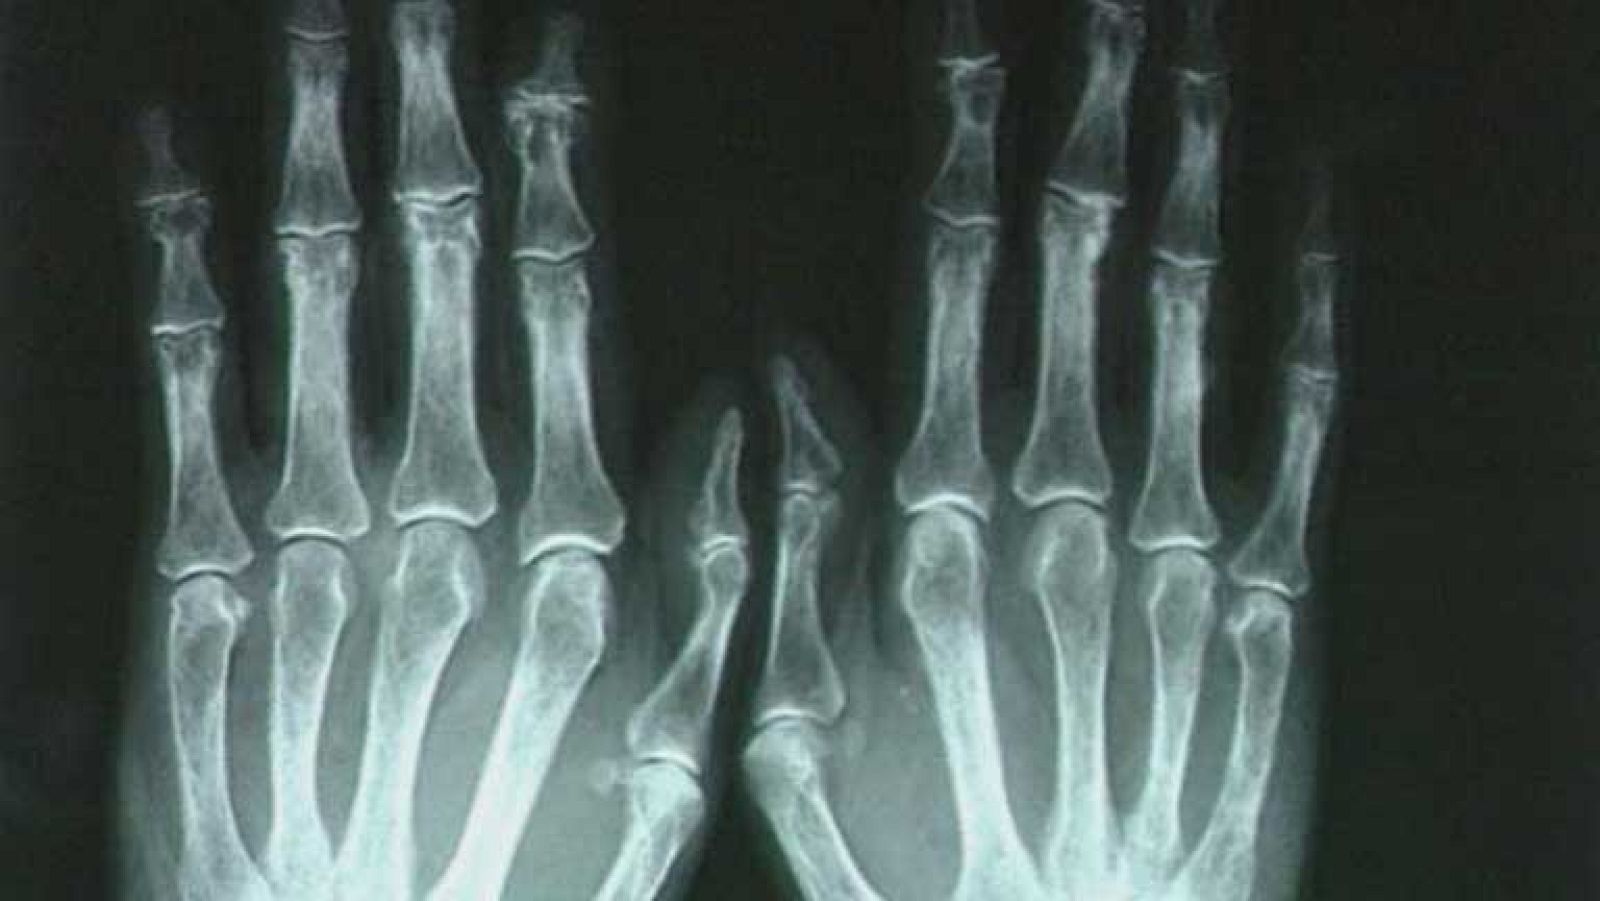

Hoy es el Día Mundial de la Artritis Reumatoide, una enfermedad de las articulaciones que en España afecta a 200.000 personas. Es muy dolorosa e incapacitante. Pero gracias a los tratamientos el pronóstico de estos enfermos ha mejorado mucho y cada vez son más los pacientes que pueden llegar a vivir sin medicarse porque la enfermedad ha remitido.